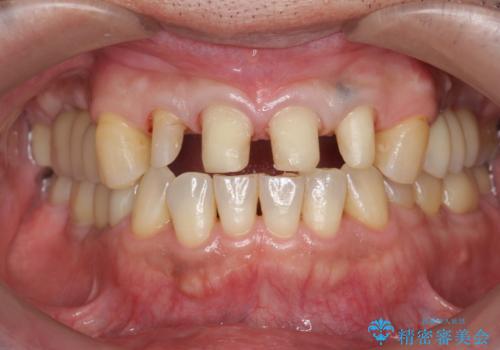

「 放置した虫歯 」 前歯セラミック治療

- 前歯の虫歯に気付きながらも放置し、一念発起し治療を希望され来院されました。

虫歯の放置により、根管治療や深い虫歯に対する処置が必要になりましたが丁寧に一つづつ処置を行ったことで抜歯をすることなく歯を残すことができました。